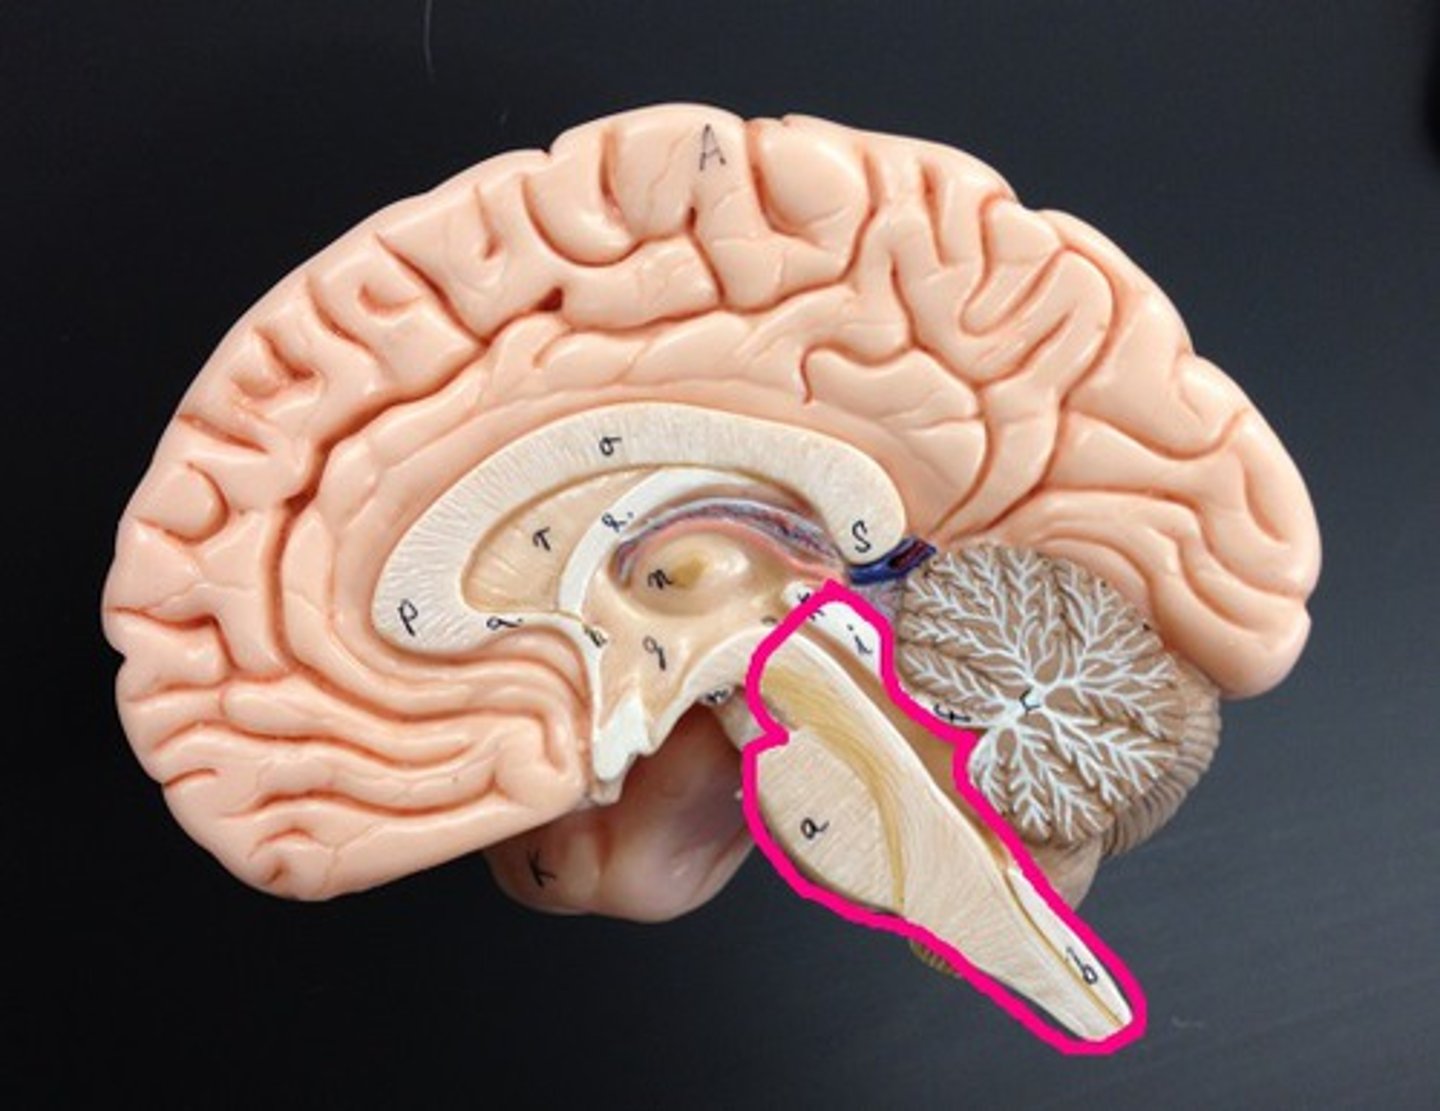

Cerebellum

Two hemispheres with convoluted surfaces,

Accounts for ~11% of total brain mass,

Provides involuntary coordination of body movements,

Also plays a role in posture and equilibrium

Cerebellum involuntary coordination

1) Receives input from motor cortex, brain stem (relays info from cortex), and sensory receptors to provide precise timing and appropriate patterns of skeletal muscle contraction,

2) Results in smooth, coordinated movements and agility (driving, walking, typing, etc.),

3) Completely subconscious (have no awareness of its functioning)

4th Ventricle